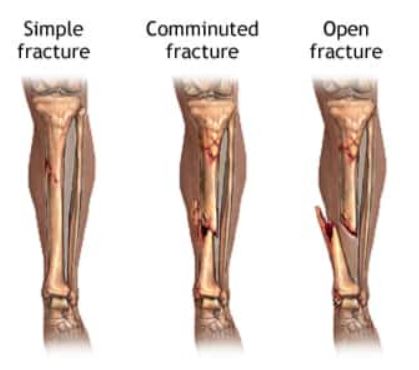

बोन फ्रॅक्चर

हाडांच्या फ्रॅक्चरचे अनेक प्रकारे वर्गीकरण केले जाते. साध्या फ्रॅक्चरमध्ये हाडातून एकच फ्रॅक्चर रेषा समाविष्ट असते. कम्युनिटेड फ्रॅक्चर म्हणजे ज्यामध्ये हाड दोन किंवा अधिक तुकड्यांमध्ये फ्रॅक्चर झाले आहे. ओपन फ्रॅक्चर म्हणजे ज्यामध्ये फ्रॅक्चर झालेले हाड त्वचेत शिरते.